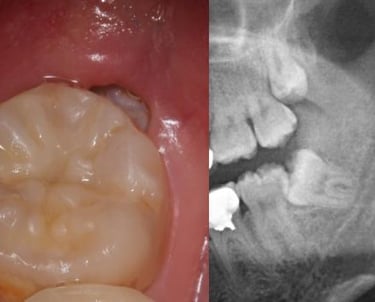

Se trata de la extracción de dientes que no han erupcionado correctamente y están atrapados en la mandíbula o el maxilar. Estos dientes pueden causar dolor, infecciones o afectar la alineación de otros dientes.

Extracción de dientes retenidos